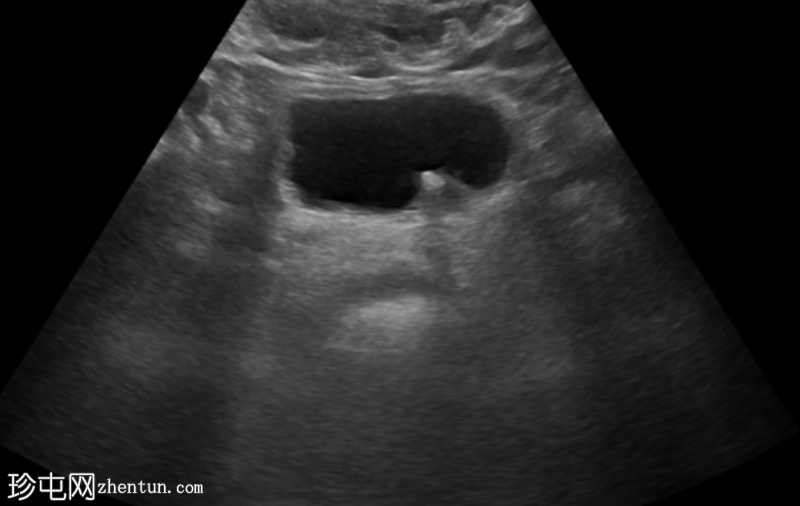

超声显示左侧轻度肾积水,由膀胱输尿管连接处一枚7毫米的远端输尿管结石阻塞所致,输尿管射流正常。

肾积水并非总是由输尿管结石引起。肾盂和肾盏扩张的程度与结石大小并不一定相关。

较小的结石有时可导致中度上游扩张,而较大的结石可能仅引起轻微的充盈感,这取决于患者的引流和水合状态。